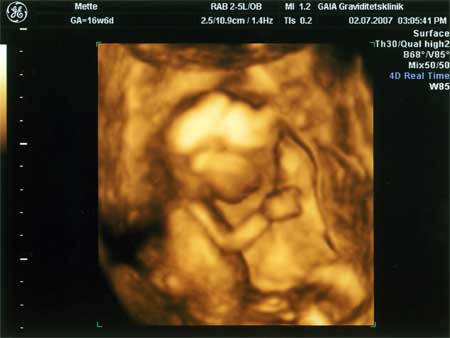

3D scanning – se baby i maven under graviditeten

3d scanning uge 16

3d scanning – uge 16

uge 16+3

En dreng :O) tappen ses meget tydeligt